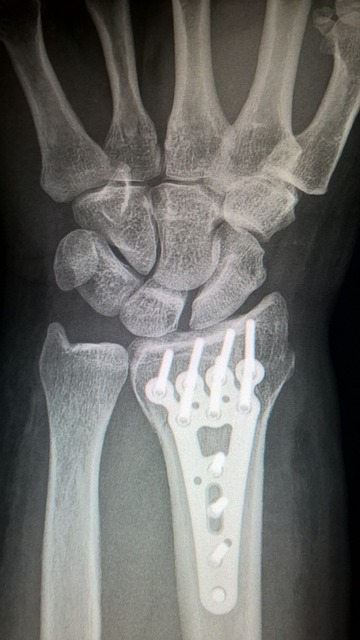

손목 통증을 치료하거나 완화하기 위해서는 먼저 통증의 원인을 정확히 파악하는 것이 중요합니다. 손목이 심하게 아프거나 저림 증상이 지속된다면, 전문의를 방문하여 정확한 진단을 받는 것이 우선입니다. 손목 터널증후군처럼 구조적인 문제가 원인일 경우, 물리치료나 약물 치료, 심할 경우 수술이 필요할 수 있습니다.